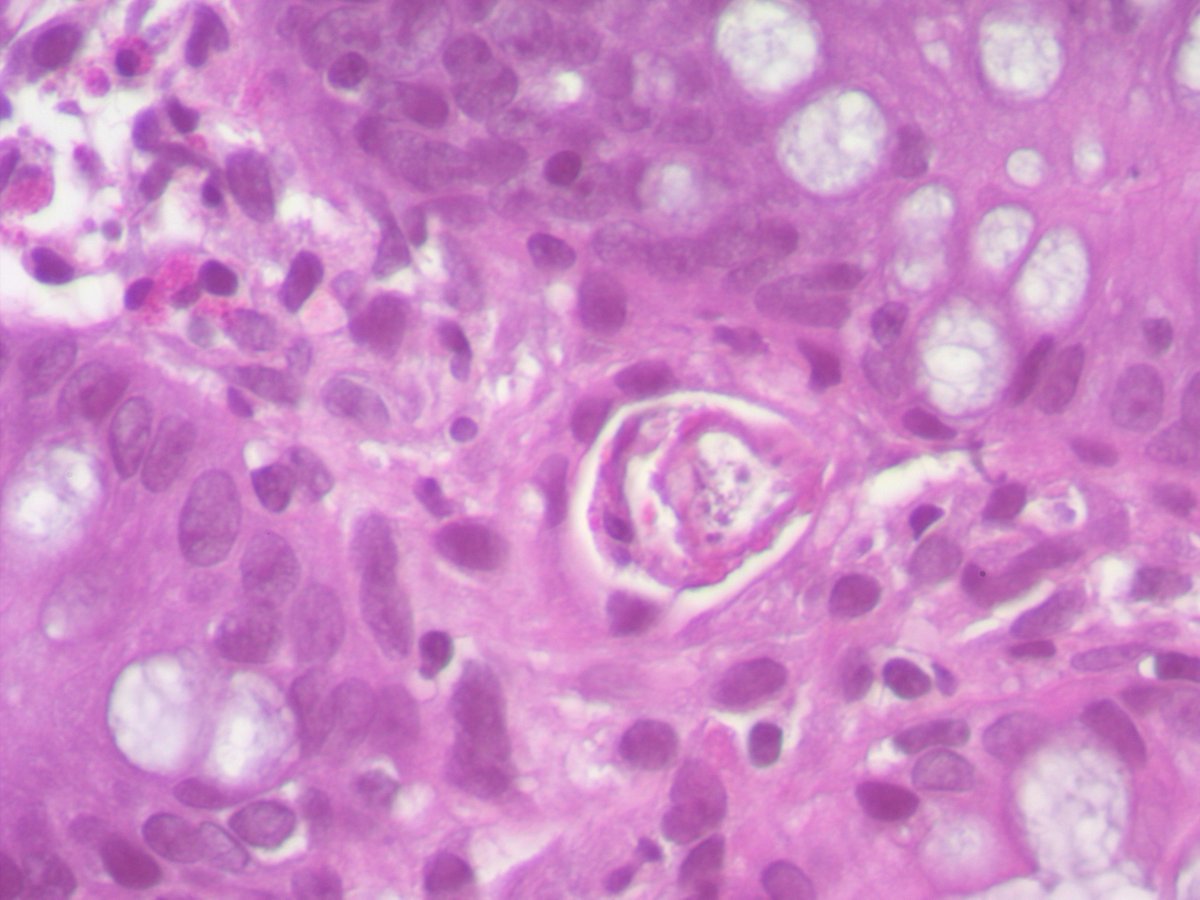

Any thoughts on this beautiful, elegant creature that "crawled" into the colonic mucosa and presented as polyp !! I have been googling it for ages and can't find a morphologic fit with any of the adult/ larval parasitic forms that I have ever encountered. Pt is asymptomatic.